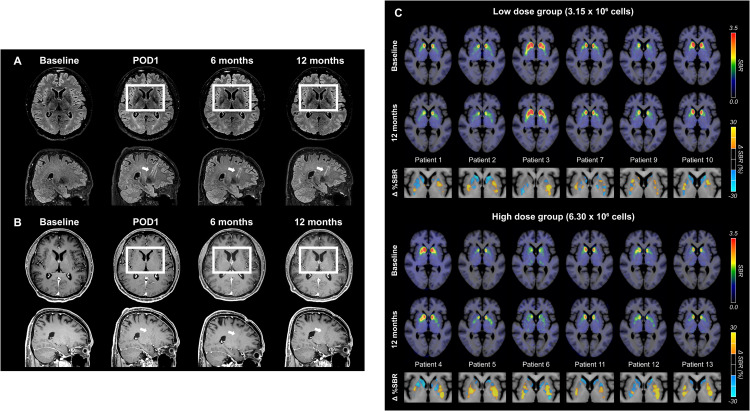

術后MRI顯示,移植區域未出現腫瘤或明顯炎癥反應,細胞被準確植入殼核目標區域,初步證明手術和細胞定位的安全性與可控性。

更關鍵的證據來自多巴胺轉運體PET成像。與基線相比,后背側殼核區域的DAT信號在高劑量組明顯升高,且這種變化與患者停藥狀態下的運動改善程度呈顯著相關。這意味著,影像學上觀察到的多巴胺能功能增強,與臨床癥狀的改善方向一致。(圖6)

這些結果共同表明:移植的多巴胺祖細胞不僅在腦內存活,而且在關鍵運動環路中實現了功能性整合,并與實際運動改善相對應。